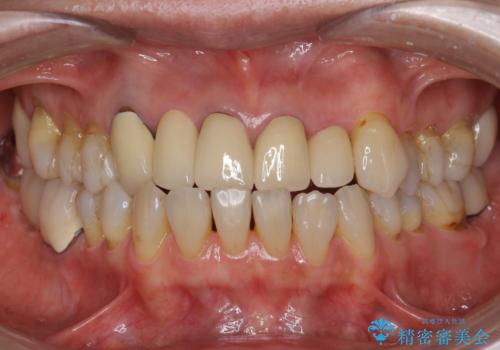

前歯のセラミック 神経の再治療から

- 他の部位の治療で来院されていましたが、30年以上前に行った前歯のかぶせ物のきわがあっておらず虫歯になってきていました。

神経の治療から念のためやり直ししてからセラミックでかぶせました。

金属の土台が入っていましたがすべて外し、ファイバーコアでやり替えています。

受け口の程度がある程度あったため、歯軸を無理にかえてかみ合わせを変えると前歯が折れる可能性があるため反対咬合は変えておりません。